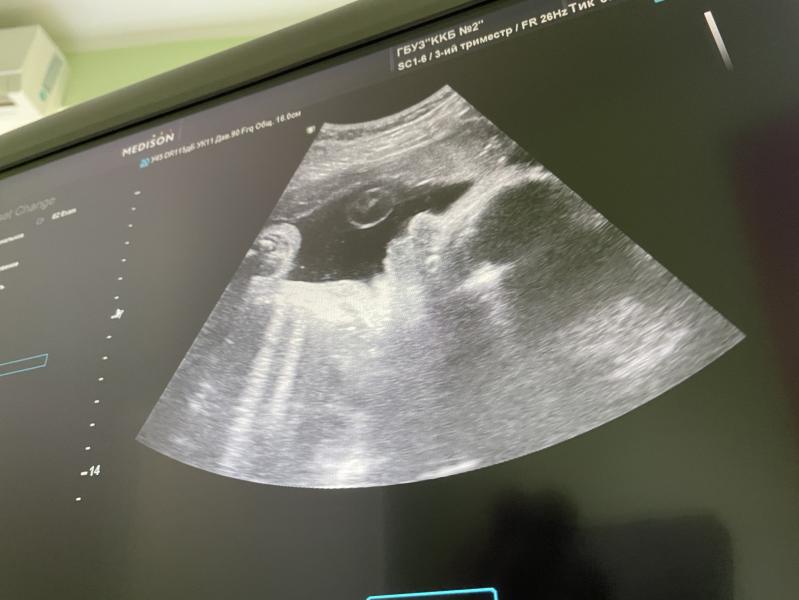

Третий скрининг ✅

Все хорошо) Лежит головой вниз и низко, перевернуться уже без вариантов (я надеюсь, так оно и есть 😅), плацента полностью поднялась 🙏 Вес предположительно 2500, опережает на недельку. Врач сказала на меня похож))